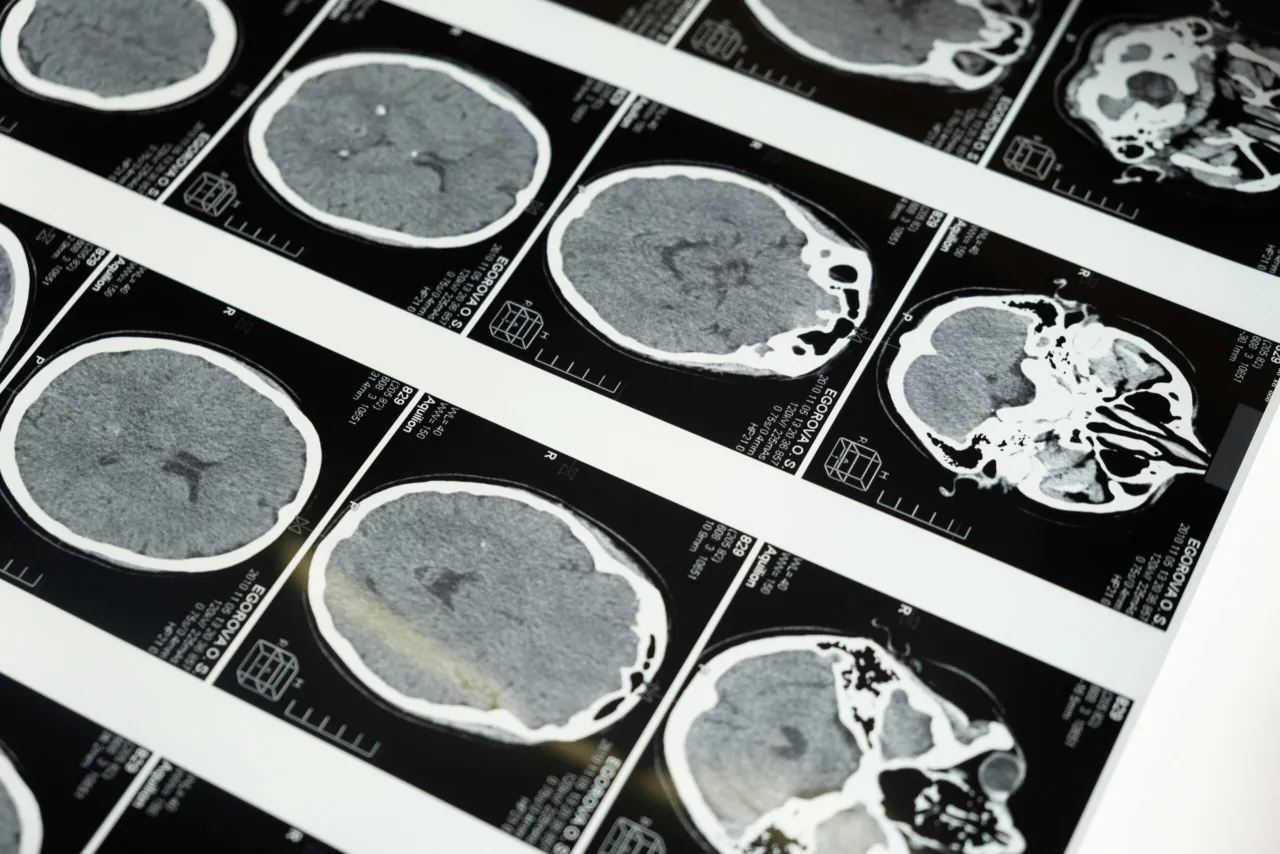

Jakie badania są kluczowe? Rola rezonansu magnetycznego i badań hormonalnych

Kluczowe badania diagnostyczne to dwa filary. Po pierwsze, rezonans magnetyczny (MRI) głowy z kontrastem. To podstawowe badanie obrazowe, które pozwala na wizualizację guza przysadki, określenie jego wielkości, lokalizacji i ewentualnego ucisku na sąsiednie struktury. Po drugie, szeroki panel badań hormonalnych z krwi. Są one niezbędne do oceny funkcji przysadki i identyfikacji ewentualnego nadmiaru lub niedoboru hormonów. Do najczęściej badanych hormonów należą: prolaktyna, kortyzol (często w dobowym profilu), ACTH, TSH, fT4 (wolna tyroksyna), FSH i LH. Wyniki tych badań pozwalają określić, czy guz jest aktywny hormonalnie i jaki typ hormonu wydziela.